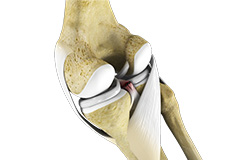

Articular Cartilage and Menisci of the Knee

Movement of the bones causes friction between the articulating surfaces. To reduce this friction, all articulating surfaces involved in the movement are covered with a white, shiny, slippery layer called articular cartilage. The articulating surface of the femoral condyles, tibial plateaus and the back of the patella are covered with this cartilage. The cartilage provides a smooth surface that facilitates easy movement.

To further reduce friction between the articulating surfaces of the bones, the knee joint is lined by a synovial membrane that produces a thick clear fluid called synovial fluid. This fluid lubricates and nourishes the cartilage and bones inside the joint capsule.

Within the knee joint, between the femur and tibia, are two C-shaped cartilaginous structures called menisci. Menisci function to provide stability to the knee by spreading the weight of the upper body across the whole surface of the tibial plateau. The menisci help in load-bearing i.e. it prevents the weight from concentrating onto a small area, which could damage the articular cartilage. The menisci also act as a cushion between the femur and tibia by absorbing the shock produced by activities such as walking, running and jumping.